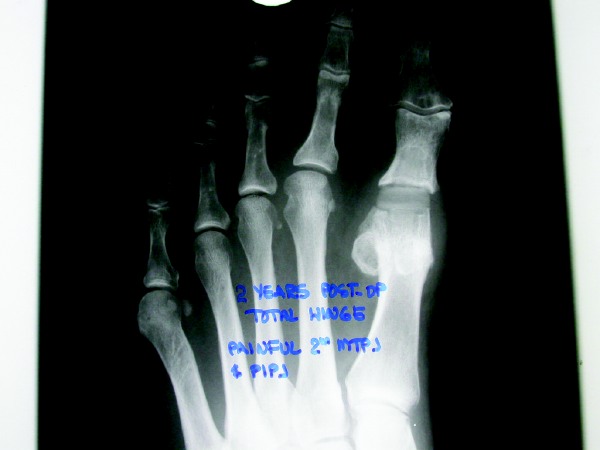

When A Patient Has A Dislocated Second MTPJ And PIPJ Contracture

If a patient has a dislocated MTPJ with contracture of the proximal interphalangeal joint (PIPJ), we may perform an open second MTPJ arthrotomy. This procedure enables us to excise inflammatory tissue, inspect the joint for cartilage damage, release soft tissue and free the plantar plate, depending upon the severity of the MTPJ dislocation. One may perform an arthroplasty of the PIPJ – or fusion if the digit is abnormally long or if the PIPJ contracture is semi-rigid or rigid – along with a flexor tendon transfer and Kirschner wire stabilization. I normally utilize the flexor brevis tendon for a second digit, which allows one to maintain the flexor longus and preserve its action on the DIPJ. If the digit is of normal length and the PIPJ contracture is reducible, clinicians may utilize an open arthrotomy of the PIPJ along with a flexor brevis tendon transfer. If there is significant redundant tissue once the digit is realigned on the sagittal plane, one may perform a plantar skin plasty, which enables you to remove an ellipse of plantar tissue from the sulcus of the second digit. This procedure also helps to maintain digital ground purchase.